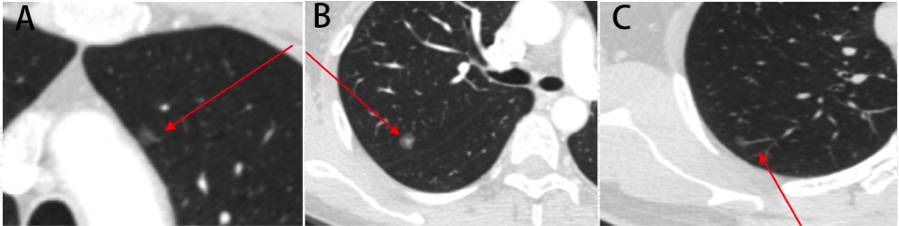

上文涉及到了Hookwire定位盲区的概念。术前Hookwire定位之后,为了便于寻找结节,定位针将短时间存于胸腔内,但手术要求在体内没有器械残留,所以术中需要将全部针道及定位针完整切除,同时在肿瘤学保证切缘阴性的基础上应尽可能保留正常肺组织,因此,针道应为结节到脏胸膜的最短距离。但在一定的区域,比如 1)距纵隔胸膜<3cm的区域(胸骨/肋软骨遮盖);2)距叶间裂<3cm的区域(需跨叶定位);3)被肩胛骨等骨性结构覆盖的区域(图2)。

图2 盲区示意图

A,纵隔胸膜附近区域;B,叶间裂附近区域;C,肩胛骨遮盖区域。